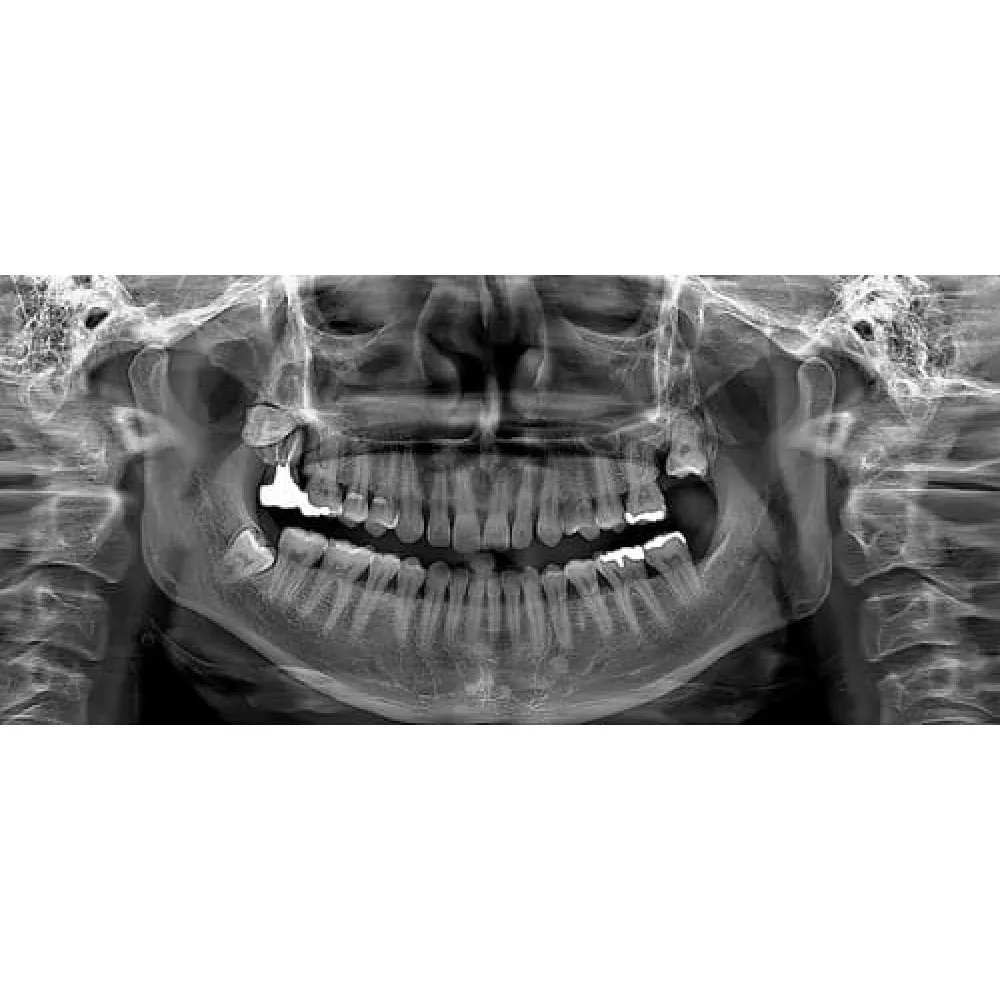

Технологии Ray обеспечивают самое лучшее качество и высокую чёткость панорамных снимков

Байт-Винг

Ортогональный

ВНЧС